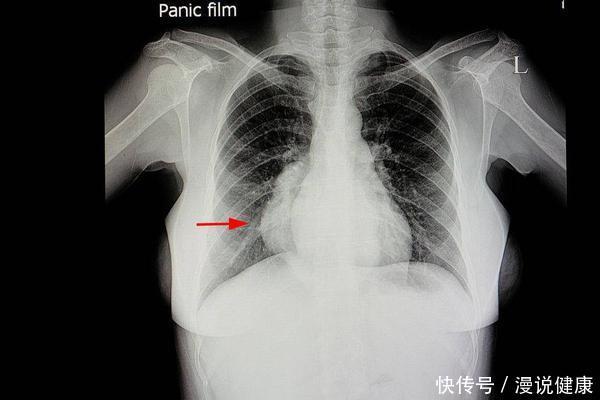

肺癌由于早期的症状是很明显,即使出现一些类似于咳嗽的症状,也很难引起人们的重视,所以很多的患者在发现疾病时都已经处于中晚期了,就会降低患者的生存率,所以在日常生活中一定要重视肺癌的预防。